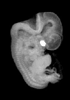

Carnegie Stage 18 (44 post-ovulatory days)

Most embryos at stage 18 are approximately 44 postovulatory days old and measure 13-17 mm in length. Distinguishing criteria for this stage include cervical and lumbar flexures, distinct notching in the hand plate, the first appearance of the elbow, eyelid folds may appear in more advanced specimens, and auricular hillocks begin to form distinct parts of the external ear.